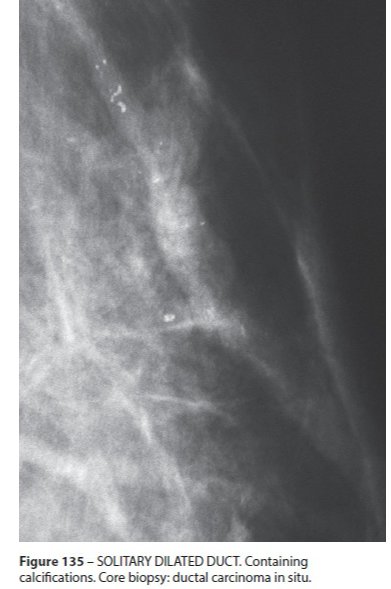

Ectasie Canlaire Solitaire

- Rare

Ectasie Canlaire Solitaire